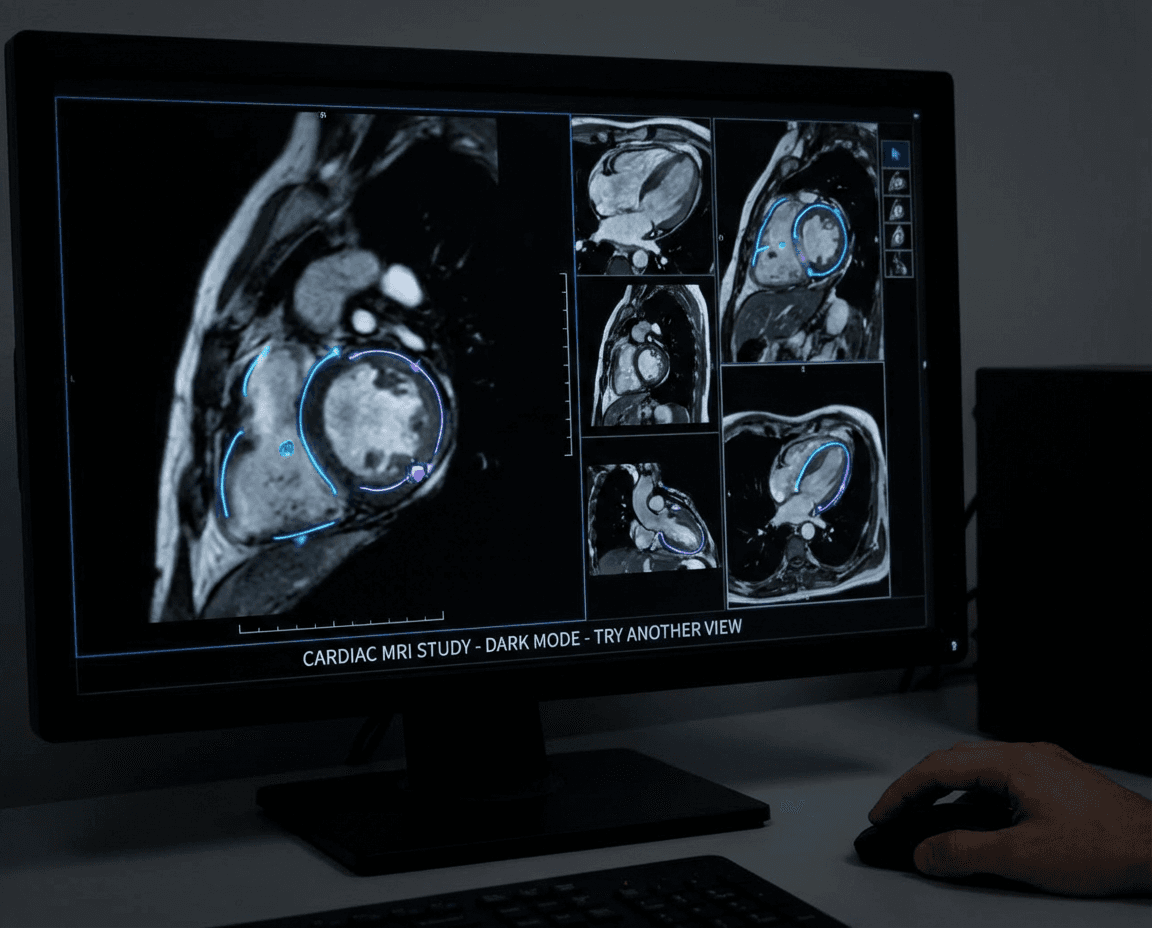

Cardiac Magnetic Resonance (CMR)

Cardiac Magnetic Resonance (CMR) imaging provides exceptional detail of heart structure, function, and tissue characteristics without radiation exposure. CMR offers comprehensive assessment of heart muscle viability, blood flow, and congenital heart defects.

Our CMR specialists utilize advanced magnetic resonance technology to provide detailed diagnostic information for complex cardiac conditions, helping guide treatment decisions and monitor disease progression with unparalleled image quality.